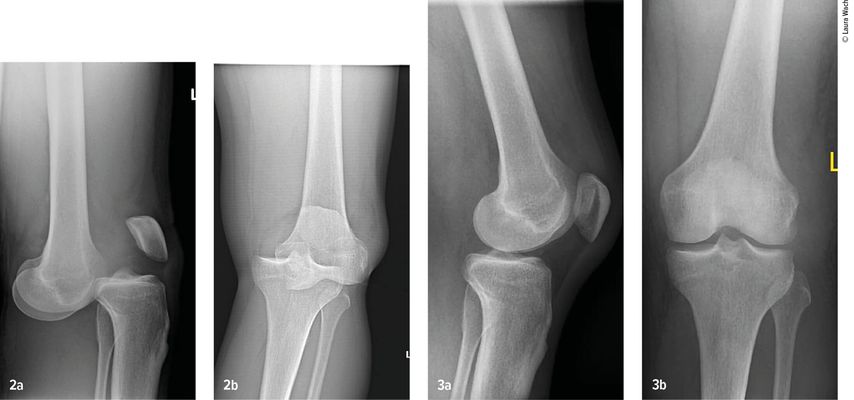

Gefäss- und Nervenverletzungen treten häufig im Zusammenhang mit einer Kniegelenkluxation auf. Henkelmann zitierte einen systematischen Review,3 der 23 Studien mit insgesamt 862 Patienten mit Kniegelenkluxationen umfasst. Bei 171 Patienten (18%) wurden Gefässverletzungen nachgewiesen. Diese kamen bei Patienten mit Schenck-Klassifikation vom Typ IIIL am häufigsten vor. Bei diesem Typ kommt es durch eine posteriore Kniegelenkluxation zur Ruptur beider Kreuzbänder und des lateralen Kollateralbandes (Abb.2 und 3). In 10 der Studien mit insgesamt 272 Patienten wurden auch Nervenverletzungen erfasst. 75 Patienten (25%) waren davon betroffen.

Abb. 2–3: Multiligamentverletzungen am jeweils linken Knie. (2) Klar ersichtlich, (3) leicht zu übersehen